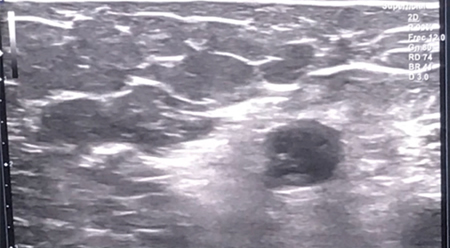

Paciente de 59 años a quien, tras rechazar la cirugía, se le realizó neurólisis ecoguiada con fenol al 6 % acuososo para el tratamiento del dolor por neuromas derivados de la amputación de ambos miembros superiores.

Figura 1

Figura 2

Figura 3